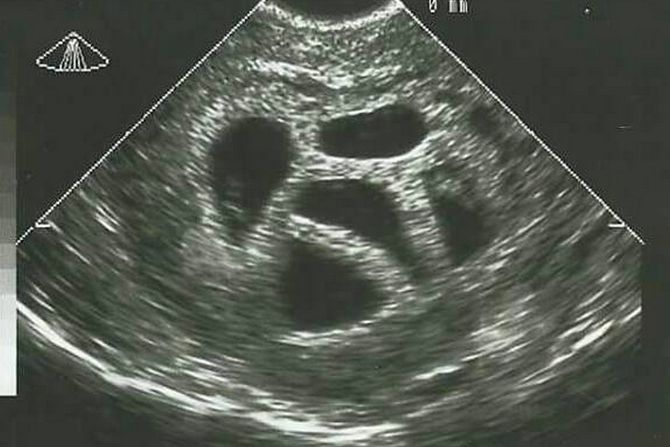

U svetu u kojem se svaka odluka o životu pretvara u debatu, priča Amerikanke Suzan Tompson vraća fokus na ono što je suštinsko - na veru, ljubav i hrabrost da se veruje u nemoguće. Imala je samo 28 godina kada je saznala da nosi petorke. Lekari su bili direktni; savetovali su joj selektivni abortus, objašnjavajući da je trudnoća rizična i da "nije realno" da sva deca prežive.

- Moj ginekolog mi je više puta predlagao da razmislim o smanjenju broja embriona - da abortiram troje, možda dvoje dece. Ali moj muž i ja nismo o tome ni pomislili. Znali smo da, ako ih je Bog poslao, On će se i pobrinuti za njih, prisetila se Suzan.